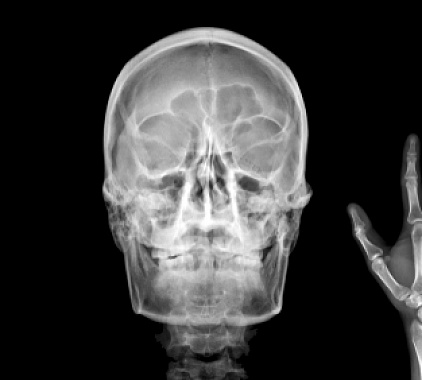

Фотогалерея

Рентген-аппарат